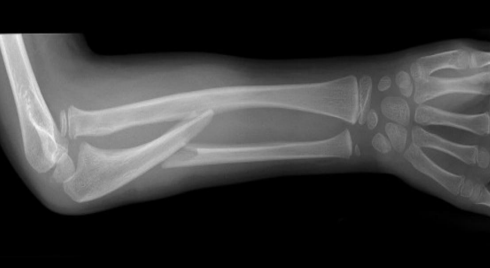

2

describe fracture

A

Extraarticular distal radius #

25% posterior displacement

45o dorsal angulation

Minimally displaced ulna styloid

How well did you know this?